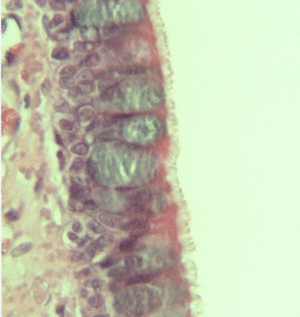

الطلائية العمودية المصففة الكاذبة Pseudo stratified Columnar Epithelium تكون هذه الطلائية من أكثر من طراز واحد من الخلايا ، فبعض هذه الخلايا طويلة ذات أسطح عريضة وقواعد نحيلة تتلامس مع الغلالة القاعدية ، والبعض الآخر من الخلايا لها عادة قواعد نحيلة ، وهي تنحشر بين خلايا الطراز الأول وترتكز أيضا على الغلالة القاعدية ، ولكنها لا تصل إلى سطح الطلائية. ويخلق إنتظام أنوية هذا الطراز في مستويات عدة إنطباعا كاذبا بأن هذا الطراز يتكون من أكثر من طبقة واحدة ، ولكنها في الحقيقة تتكون من طبقة واحدة من الخلايا.

يبطن هذا الطراز من الطلائية القنوات الإخراجية الكبيرة للغدد كما هو الحال في الغدة النكافية ، وهي تبطن أيضا الجزء العلوي من الوعاء الناقل ومجرى البول الذكري والبربخ.